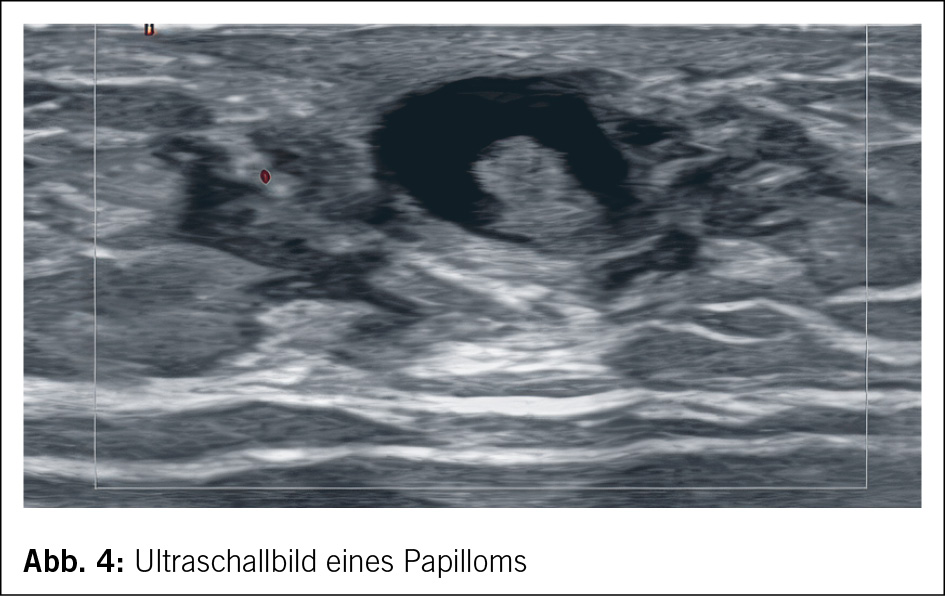

Papilläre Neoplasien treten bei Männern sehr selten auf. In der Literatur finden sich nur wenige Fallbeschreibungen. Eine retrospektive Datenbankanalyse über 19 Jahre konnte 117 Männer mit einer papillären Neoplasie identifizieren. Diese Studie konnte aufzeigen, dass papilläre Neoplasien ohne Atypien insbesondere bei jungen Männern auftreten und insgesamt sehr selten sind. Der grösste Anteil der papillären Neoplasien war mit einem DCIS oder einem Karzinom assoziiert (6). Abb. 4 zeigt ein Papillom bei einem 34-jährigen Mann, der sich aufgrund eines Tastbefundes vorstellte. Der Befund wurde mit einer sonografisch gesteuerten Stanzbiopsie abgeklärt und bei fehlenden Atypien mittels sonografisch gesteuerter Vakuumbiopsie entfernt.